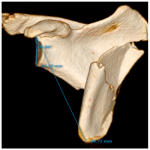

578

Reducción abierta y fijación interna como manejo de una fractura compleja de escápula en una niña con politraumatismos. Reporte de un caso

Danilo Mesa Rincón, Andrea Gamarra Patrón, María Fernanda Ochoa Ariza, Sergio R. Gómez

604

Resolución del caso

Bibiana Dello Russo, Mónica Galeano, Florencia D´Adamo